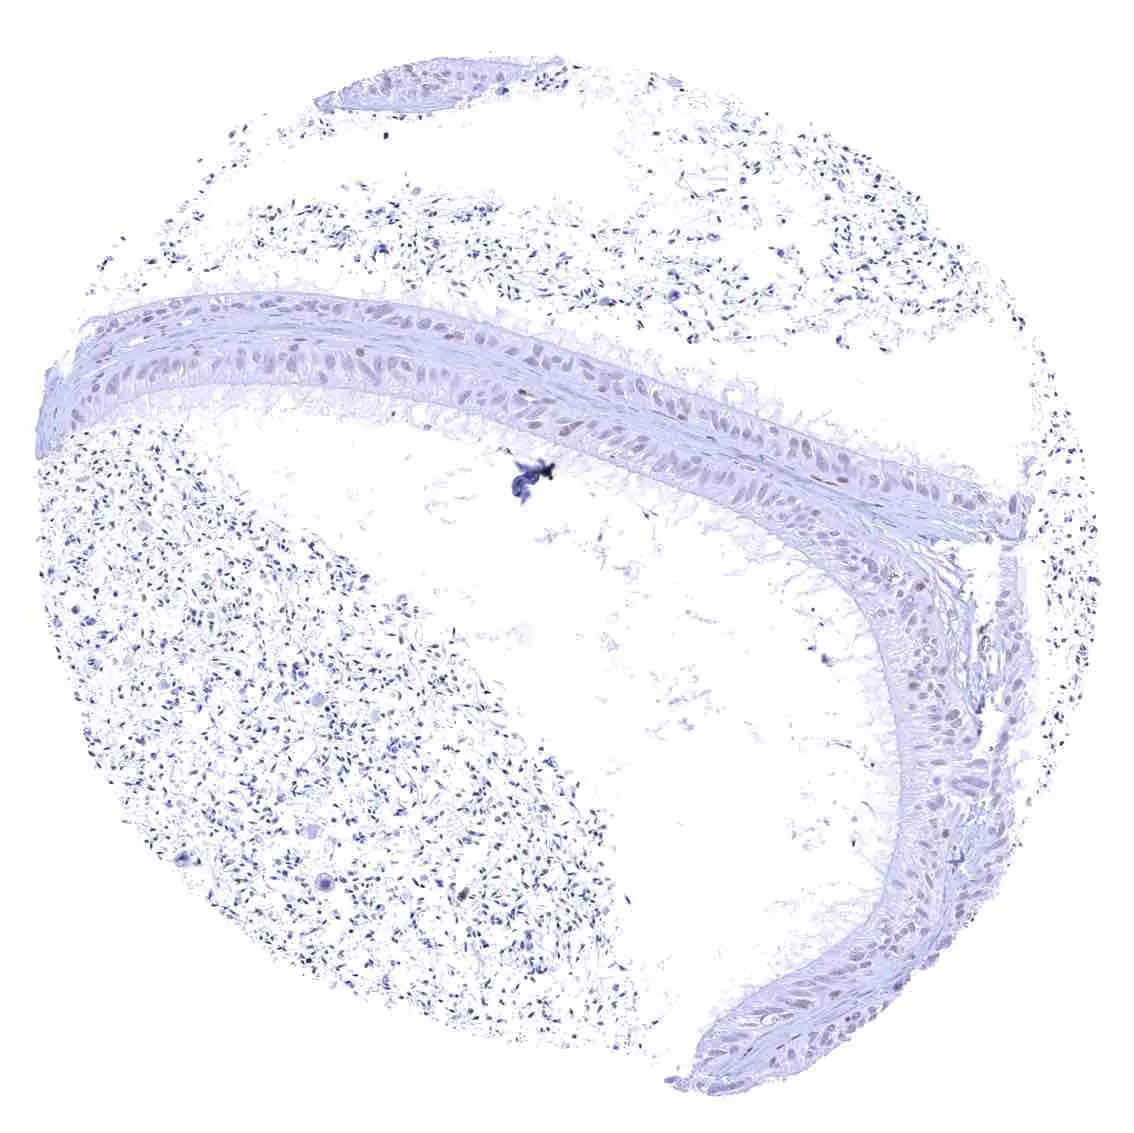

Aorta, media – Strong nuclear p27 staining of muscle cells in the aorta.